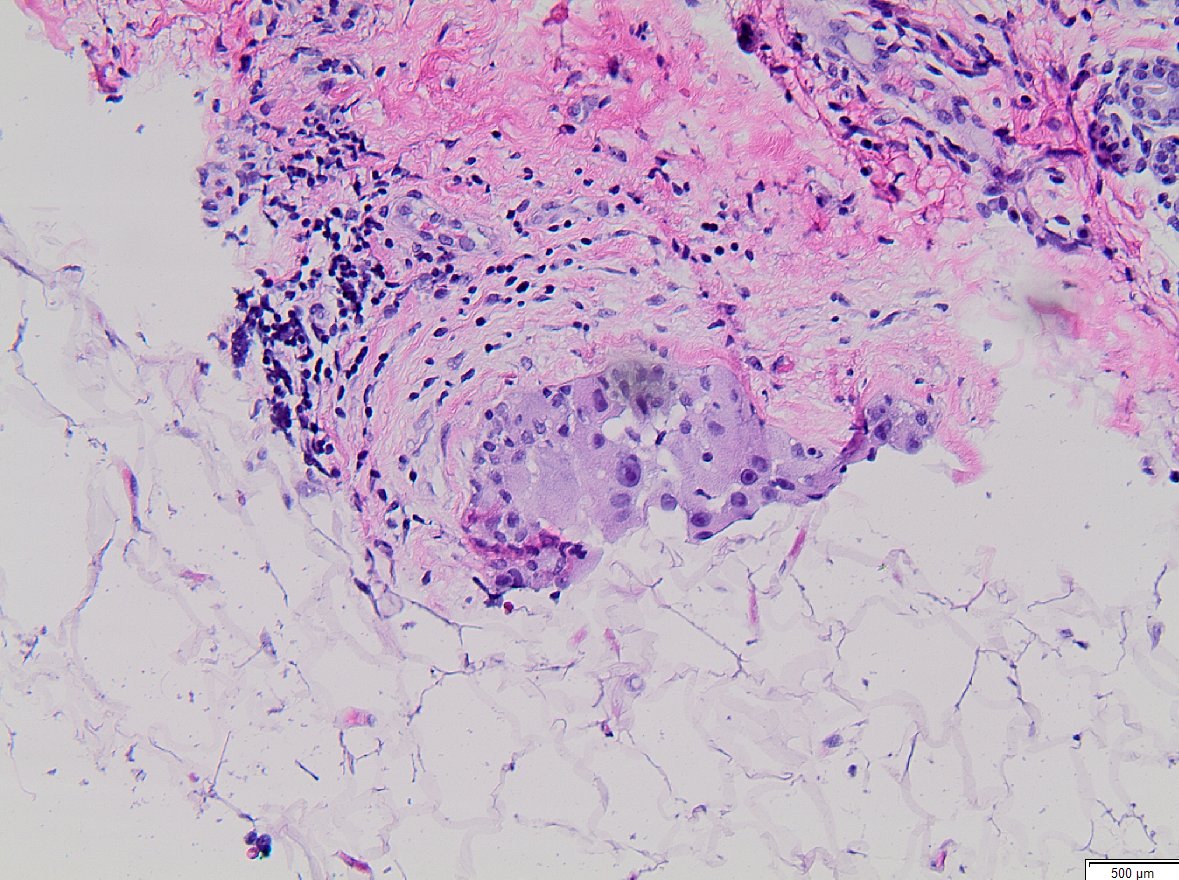

Pathologist at Royal Adelaide Hospital | Professor @UniofAdelaide | Interested in breast & soft tissue pathology, breast cancer screening & digital pathology